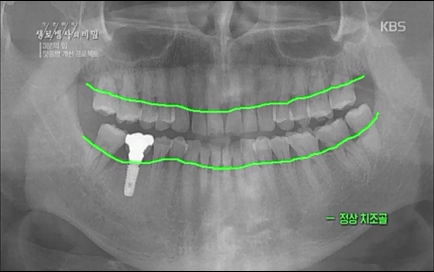

3분의 힘 잇몸병 개선 프로젝트